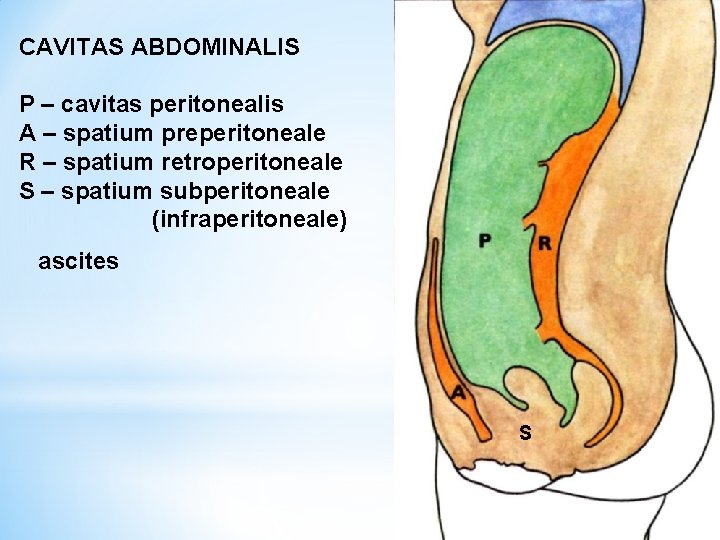

CAVITAS ABDOMINALIS P – cavitas peritonealis A – spatium preperitoneale R – spatium retroperitoneale S – spatium subperitoneale (infraperitoneale) ascites S